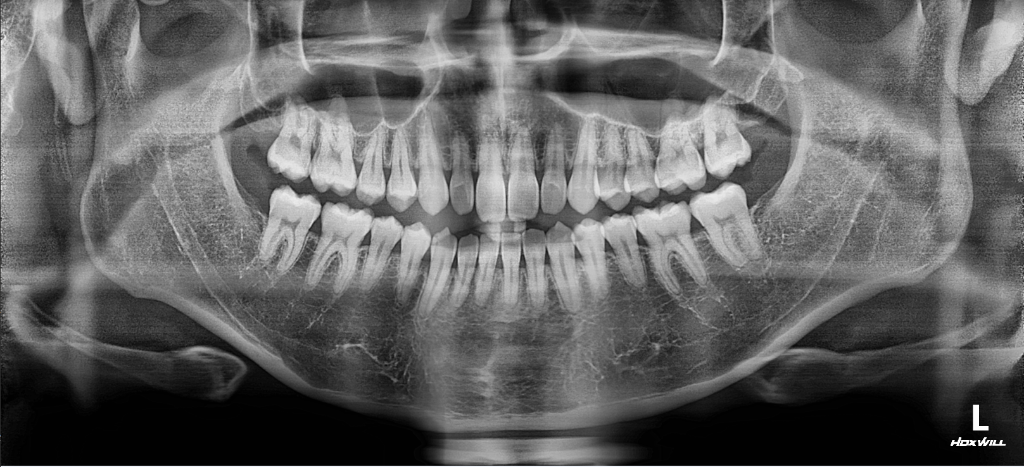

턱이 비율상 대각으로 긴가요?

사진찍으면 턱이 대각으로 긴 느낌과 돌출입 느낌이 있어서 대략적인 판단부탁드립니다

• 2번 째 사진

해당 골격 정도로는 비대칭이라고 보지 않습니다. 너무 예민하게 반응하시는 것으로 보이며 이정도는 정상 범주입니다. 연조직을 보지 않더라도 심미적으로 크게 문제가 되지 않을 것으로 보이며 미세 조정을 원한다면 담당 교정과 선생님과 상담을 해보시길 바랍니다.

사진상으로는 크게 문제는 없어 보입니다. 정확한 판단을 위해서는 교정진단을 통해서 정상 범주와 비교를 해보는게 좋습니다.